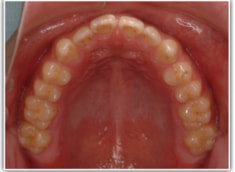

開咬(かいこう:オープンバイト)ケース

治療法:表の矯正(T21ブラケット)

(インプラントアンカーや外科矯正は行わず、エラスティックと機能訓練のみ)

治療後(2年2ヶ月後)